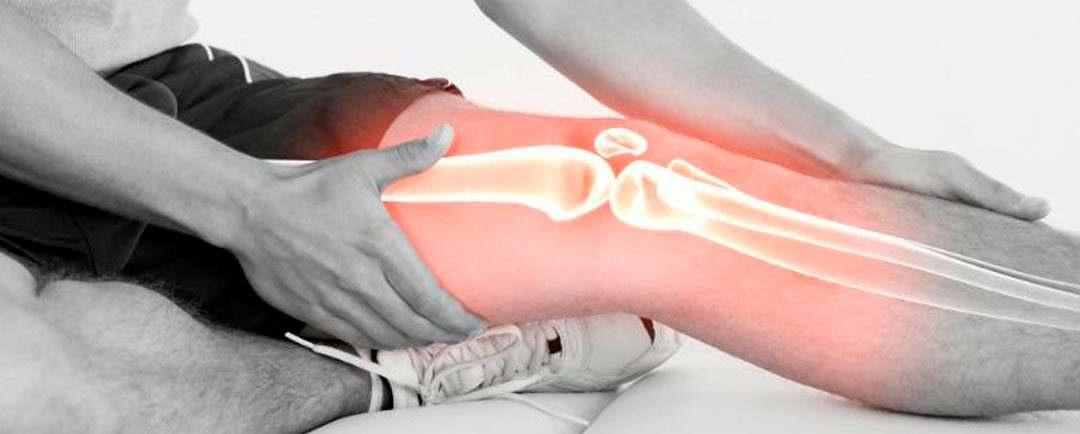

Las lesiones del complejo posteroexterno (CPE) son de una frecuencia significativa de las lesiones ligamentariasdelarodilla.

Lasospecharequierecomprensióndelasestructuras,su biomecánicaylasposiblesopcionesdetratamiento

Un mecanismo común de lesión es un golpe directo a la rodilla desde la región anteromedial; Sin embargo, los mecanismos de hiperextensión forzada y de estrés en varotambiénpuedendañarelCPE.

Los síntomas con mayor frecuencia son dolor, equimosis e inflamación; la percepción de inestabilidad principalmente a la extensión completa y una mayor dificultad para caminar sobre terreno irregular o al subir ybajarescaleras.

Se justifica un examen minucioso de una posible lesión en el CPE en toda lesión de los ligamentos cruzados comolesiónacompañante.

Esesencialobtenerradiografíasdeestrésenvaroparael diagnóstico objetivo de lesiones del CPE y la resonancia magnética (MRI) se debe realizar para ayudar en el diagnóstico de las lesiones agudas, lesiones asociadas ydeterminarlaubicacióndelasestructurasdañadas. La elección del tratamiento (quirúrgico y no quirúrgico) corresponde al grado de lesión así como al tiempo de la lesión del CPE y es de importancia el periodo de rehablitaciónacompañante.

Acudir a una correcta valoración con su médico de confianzaesrecomendable.